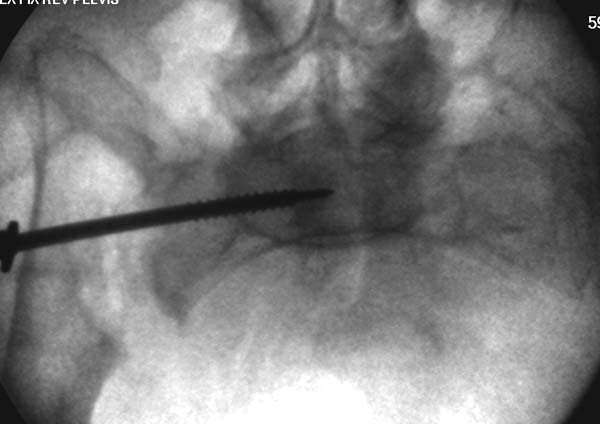

Здесь снимки, которые показывают направление стержня, а также идею

репозиции вытяжением. На рентгенопроницаемых столах имеется возможность

установить дополнительную раму, где по желанию можно увеличить или

уменьшить высоту угла вытяжения. Для репозиции таза больной в положение

на спине, стержень для вытяжения остается во время операции. Система

подойдет для тракции головки бедра из вертлужной впадины, и для этого

стерильная веревка и Synthes Universal Chuck with T-Handle.